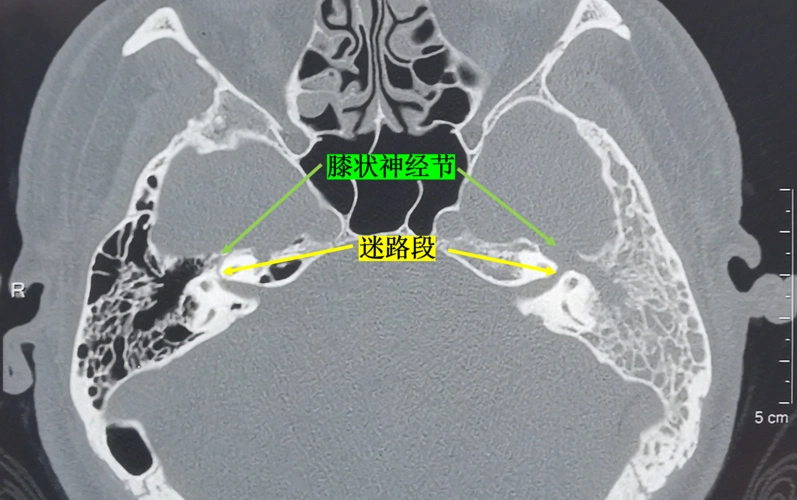

面神经瘤的影像学特点